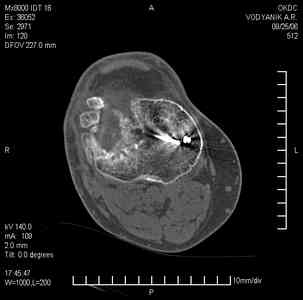

Тугой ложный сустав правого бедра в сочетании неправильно сросшимся переломом большеберцовой кости |

Уважаемые коллеги,В ортопедическое отделение обратился пациент: мужчина 47 лет, который в течение 4-х лет дваждыполучил травму костей, образующих правый коленный сустав. В 2002 v внутрисуставной оскольчатыйперелом проксимального метаэпифиза правой большеберцовой кости; в 2005 v внутрисуставнойоскольчатый перелом дистального метаэпифиза правой бедренной кости. В обоих случаях в разных лечебных учреждениях проводилось оперативное лечение переломов.При осмотре в отделении на основании результатов клинического осмотра и данных визуальныхметодов обследования поставлен диагноз:тугой ложный сустав дистальной трети правой бедренной кости, состояние после накостногоостеосинтеза перелома типа 33-В2.2 ; несросшийся перелом надколенника; неправильно сросшийсяперелом латерального мыщелка правой большеберцовой кости, состояние после металлоостеосинтезаперелома 41-В2.2; сочетанная осевая деформация правой ноги: варусная деформация правого бедра,вальгусная деформация правой голени; посттравматический артроз коленного сустава 4 ст по Kellgren-Lowrence; выраженное нарушение функции ходьбы и опоры. Внешний вид ноги больного, данные рентгенографического обследования и избирательно выделенные компьютерные томограммы приведены в приложении. В именах КТ использовано кодирование уровня по АО, т.е. _41, например, означает проксимальную треть голени.В отделении намечен v очень предварительно v следующий план лечения: 1. Иметь ввиду перспективу тотального эндопротезирования коленного сустава. 2. С учетом п.1 при проведении действий, направленных на устранение ложного сустава бедренной кости не использовать материалы, не подвергающиеся трансформации. 3. В ходе операции, направленной на устранение ложного сустава: А. удалить все металлоконструкции; Б. ревизовать зону пролежня под пластиной на бедре, при наличии признаков достаточной жизнеспособности кости выполнить остеопериостальную декортикацию, дрилинг ложа пластины; В. Удалить рубцовую ткань по плоскости ложного сустава, и в пространстве между костными форагментами, насечь обращенные друг к другу поверхности. Ввести штифт с блокированием (например Stryker с учетом особенностей расположения дистальных блокирующих винтов у этойконструкции). Осуществить остеосинтез с учтанением варусной деформации бедренной кости. Пространство в зоне ложного сустава и пустоты в метафизе бедренной кости заполнить резорбирующимся цементом на основе гидроксиапатита кальция. Для дистальной фиксации использовать винты с переменным шагом резьбы. Вариант:, винты вводить после заполнения метафиза цементом. Дополнительные виды создания межфрагментарной компрессии во встречно-боковом направлении обсуждаются. Г. Быть готовым к кровопотере. Д. Учесть высокий риск инфекции, тромбоэмболических осложнений. Е. Вопрос о внешней иммобилизации решить по результатам оценки стабильности остеосинтеза. Вариант - одноосевой стержневой аппарат для шунтирования гвоздя с модулем на голени и дистракцией коленного сустава в течение 3-5 недель. Просим вашей критики намеченного плана и конструктивных предложений. С уважением к сообществу, Ординатор В.С. Саплин

Движения приличные, есть за что бороться. Такая ротация голени кнаружи, если она действительно есть (для уточнения можно сделать КТ на уровне обоих метафизов и бедреных, и берцовых ксотей, не меняя положение ног во время съемки), большого значения не имеет. А уж на фоне всего остального тут - вообще говорить не о чем.